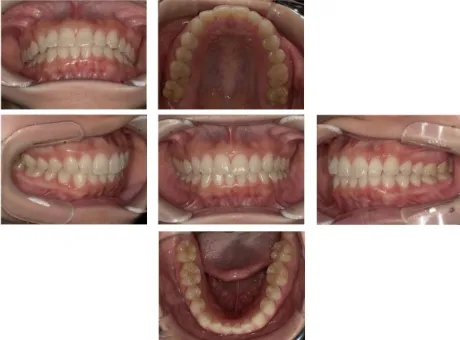

- お口のスナップ写真

- レントゲンではわからない歯肉の状態や、歯のかみ合わせや歯並び等レントゲンではわからない問題などを確認できます。

レントゲンだけではわかりづらいこともお口の写真をみながらご説明することでとてもわかりやすくなります。